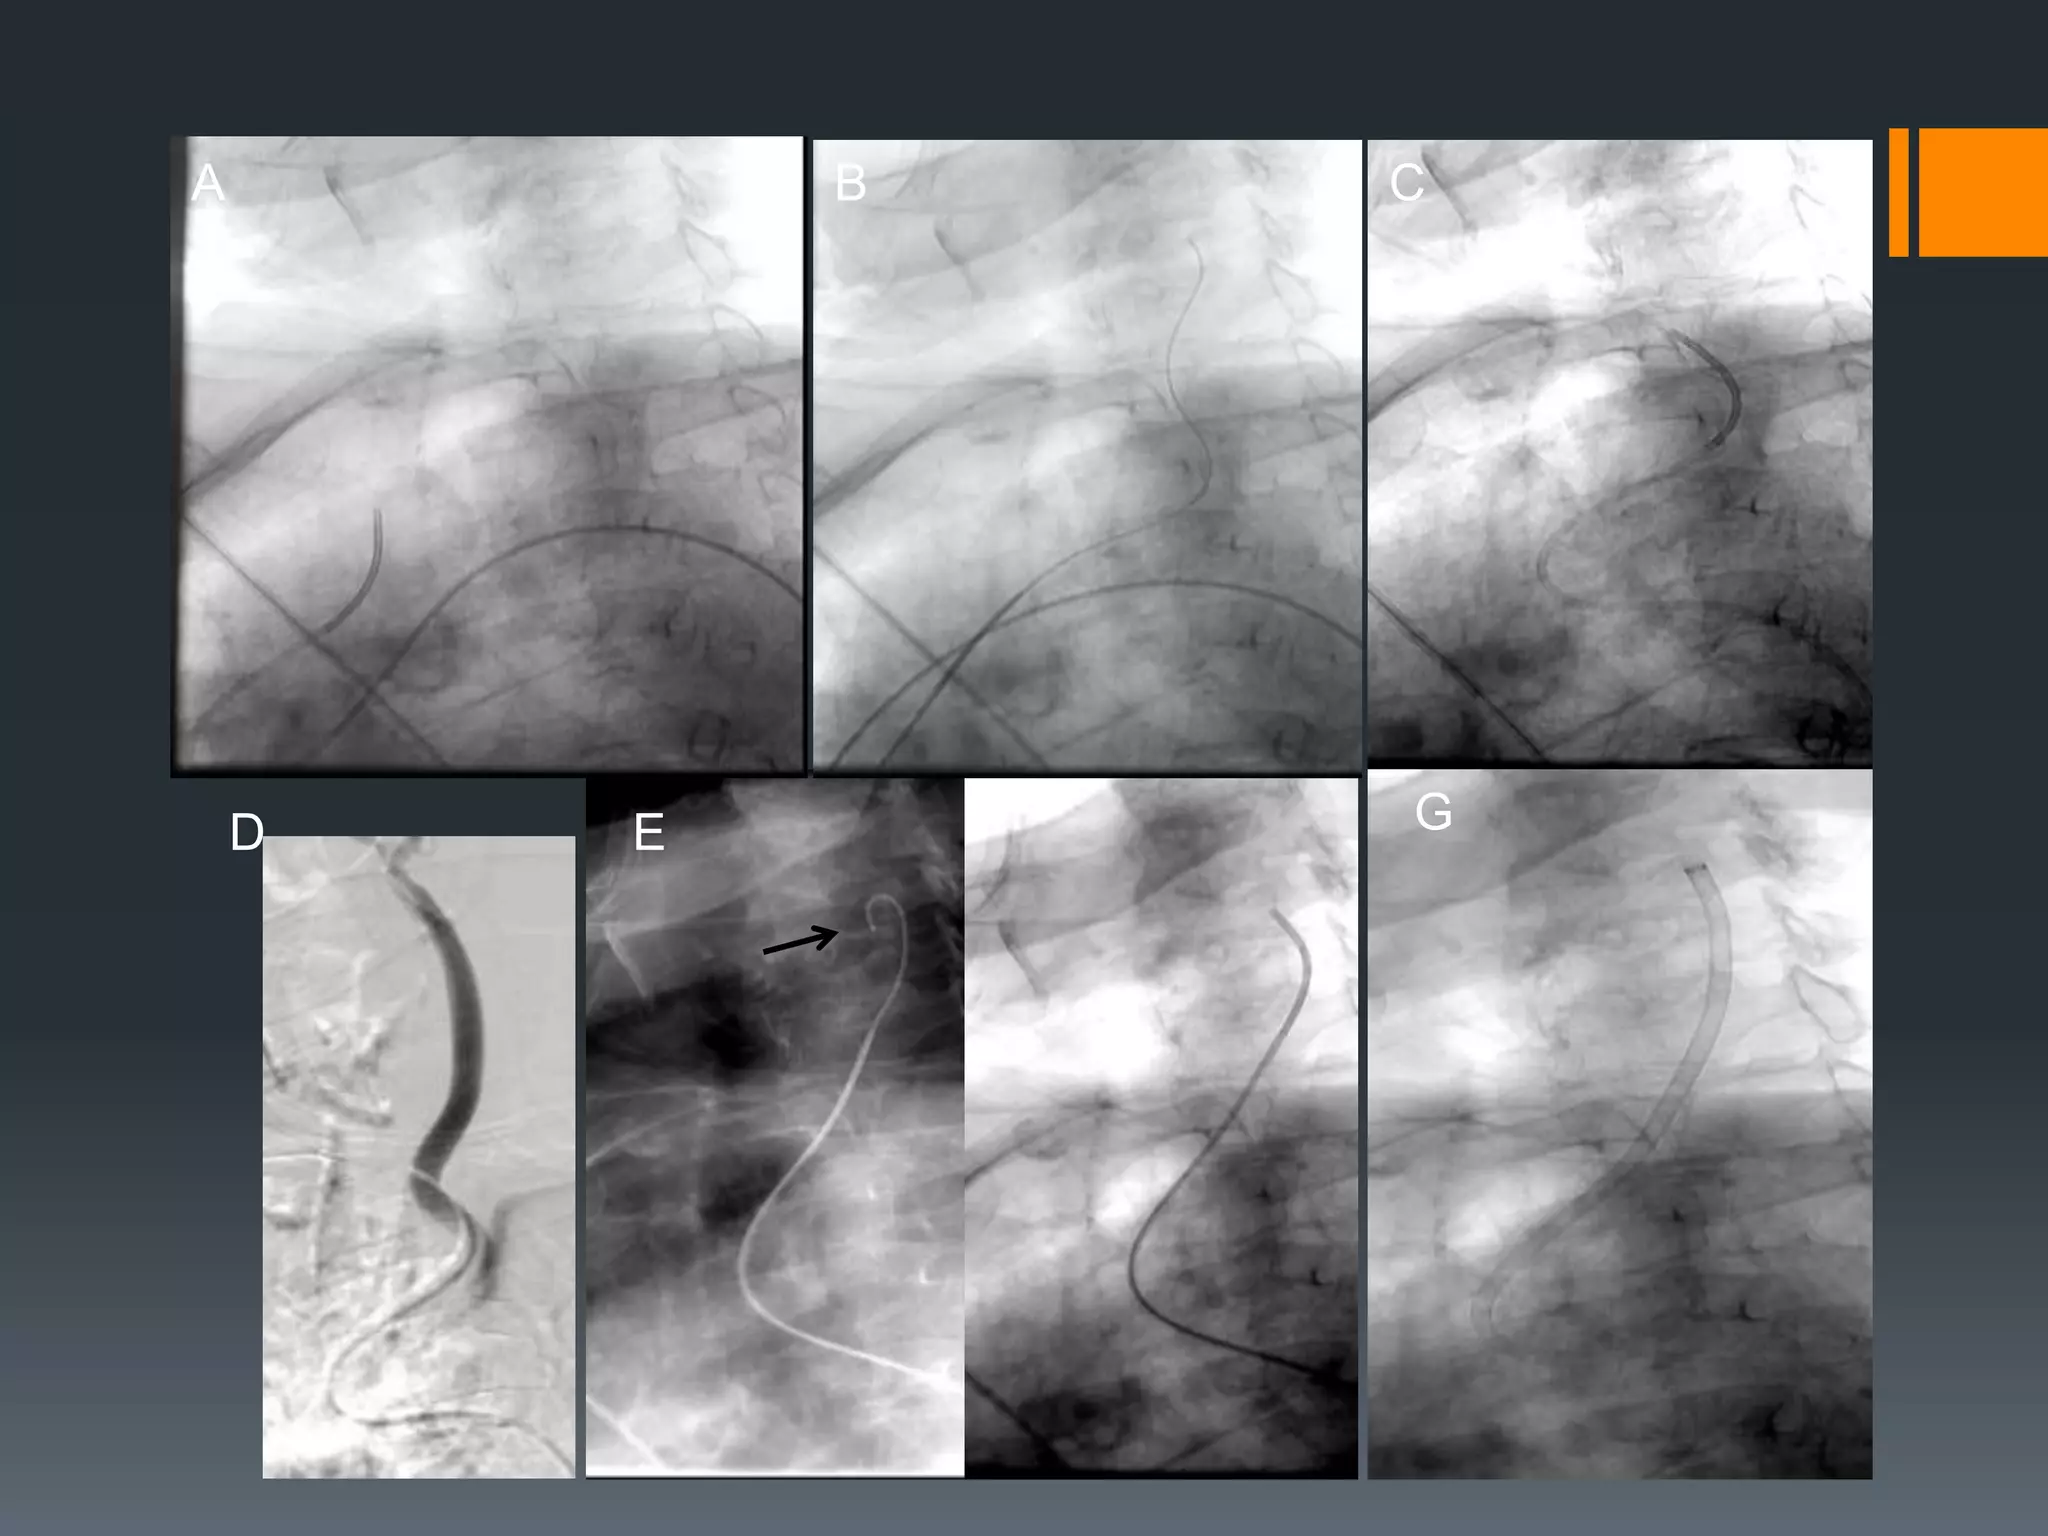

This document discusses tricks and techniques for difficult cannulations during neurointerventional procedures. It outlines strategies for accessing the aortic arch, internal carotid artery (ICA), and areas distal to aneurysms. Long sheaths, distal access catheters, and co-axial techniques are presented as options that have improved cannulation success. Guidance on sheath and catheter selection is provided for different vessel paths. The importance of catheter placement as high as possible in the ICA is emphasized. Reverse curve cannulations are also mentioned. Overall, the document stresses that careful cannulation is critical for procedural success and different strategies may be needed depending on the vessel target.